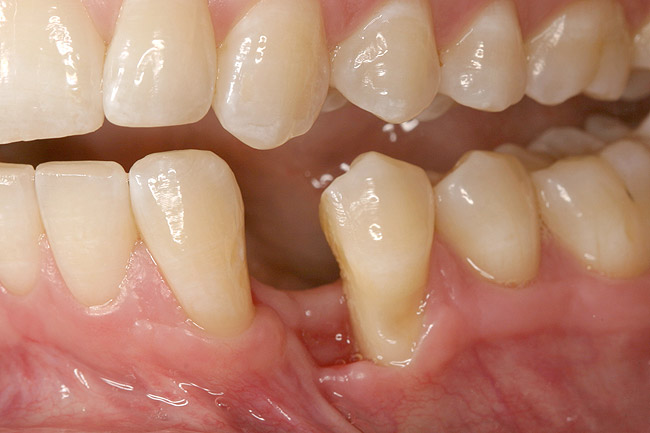

A 28-year-old Caucasian female presented to the periodontist with a complaint of a mobile implant in the site of tooth No. 22 (Figure 2 and Figure 3). The patient had a congenitally missing tooth No. 23. No. 22 had erupted into site No. 23, leaving a vacancy at site No. 22, and was the reason for the original implant at site No. 22.

Figure 2  A preoperative retracted anterior view of the failing implant in the site of tooth No. 22.

Figure 2